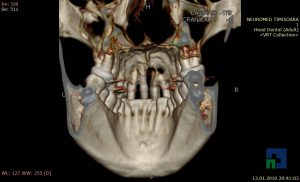

- Diagnosticul traumatismelor de bază de craniu

- Diagnosticul fracturilor:

- Complexe cranio-sinusale

- Complexe cranio-etmoidale

- Complexe cranio-orbitare

- Complexe cranio-faciale